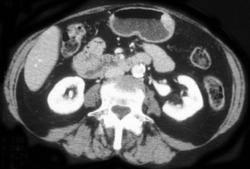

Pneumoperitoneum Due to Perforated Gastric Ulcer